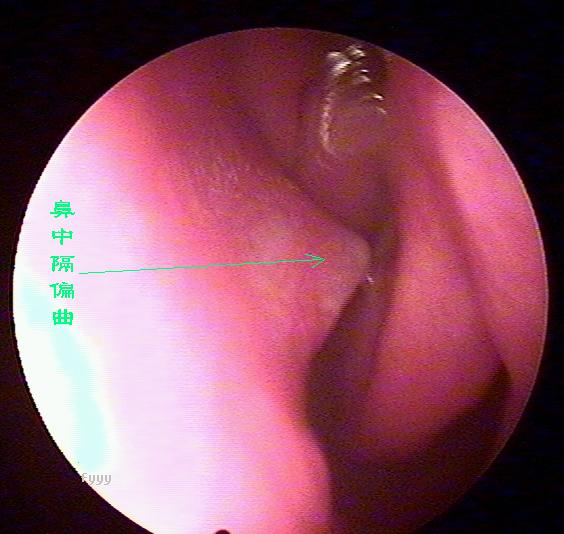

鼻中隔偏曲的诊断检查

鼻中隔偏曲进行鼻内检查以判断鼻中隔偏曲的类型和程度,注意鉴别鼻中隔粘膜肥厚和是否同时存在鼻内其它疾病,如原发病变—肿瘤、异物或继发病变—鼻窦炎、息肉等。 另一罕见者为鼻中隔梅毒瘤,其质地中亦较硬,但该处粘膜明显充血。